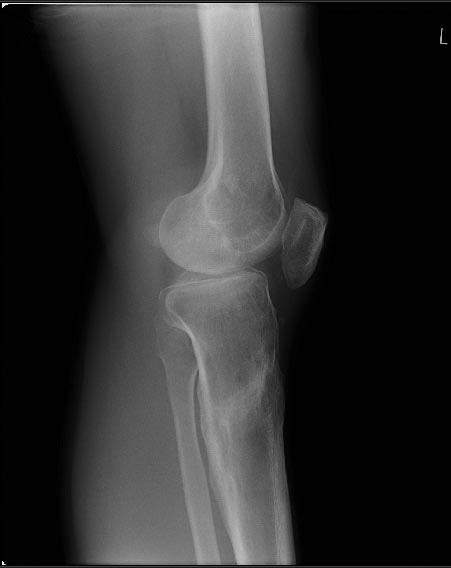

Друзья - коллеги, Пациент 27 лет приехал для удлинения роста по эстетическим показаниям. Метод: крослатеральное двухэтапное удлинение голеней 4см и бедер 3 см. Между этапами удлинения уезжал к себе домой в Японию на реабилитацию. Между этапами удлинения движения в коленных суставах разгибание полное сгибание 90-85. После выписки (февраль 2012) даны соответствующие указание постепенно возрастающей нагрузки и ЛФК коленных суставов.

В настоящий момент жалобы на ограничение сгибания в коленных суставах. Снимки прилагаются.

Вопрос: почему возникло такое осложнение? Поверьте приходилось удлинять намного больше, а тут всего на 3-4 см и такое осложнение на обеих конечностях у одного пациента?

Что можно сделать? У кого есть опыт лечения patella baja?

Возможно( ни в чем не уверен) но причина ,что пошли высоковато ,через бугристось на голенях и собственная связка так же вытягивалась, смещая надколенник вниз? На рентгене же связки оссифицированы,больше справа.

Высылаю снимки, свидетельствующие, что уровень остеотомий вроде как обычный, повторюсь, подобного осложнения после удлинения я не встречал ни у себя ни

в литературе. Сейчас на первое место встает вопрос как помочь данному пациенту. У кого есть опыт лечения patella baja?

Остеотомия высокая, почти на уровне бугристости, так что область прикрепления связки надколенника близко. Я бы делал на 2-3 см ниже. Удлинять на уровне диафиза стало особенно актуально в свете смены аппарата на гвоздь по окончании удлинения.